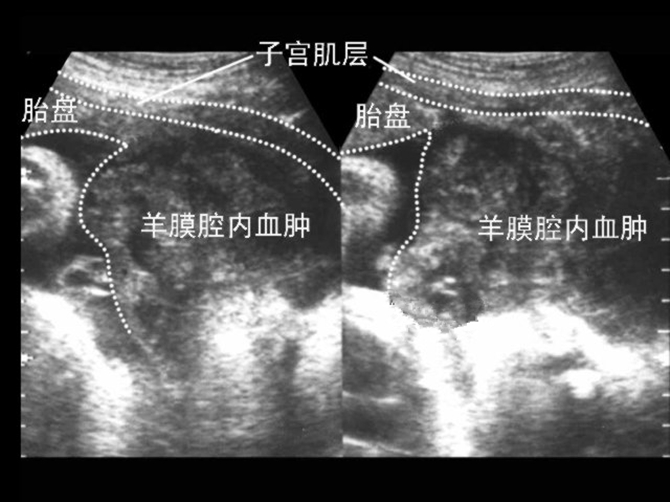

胎盤早剝超聲診斷

胎盤早剝血腫超聲